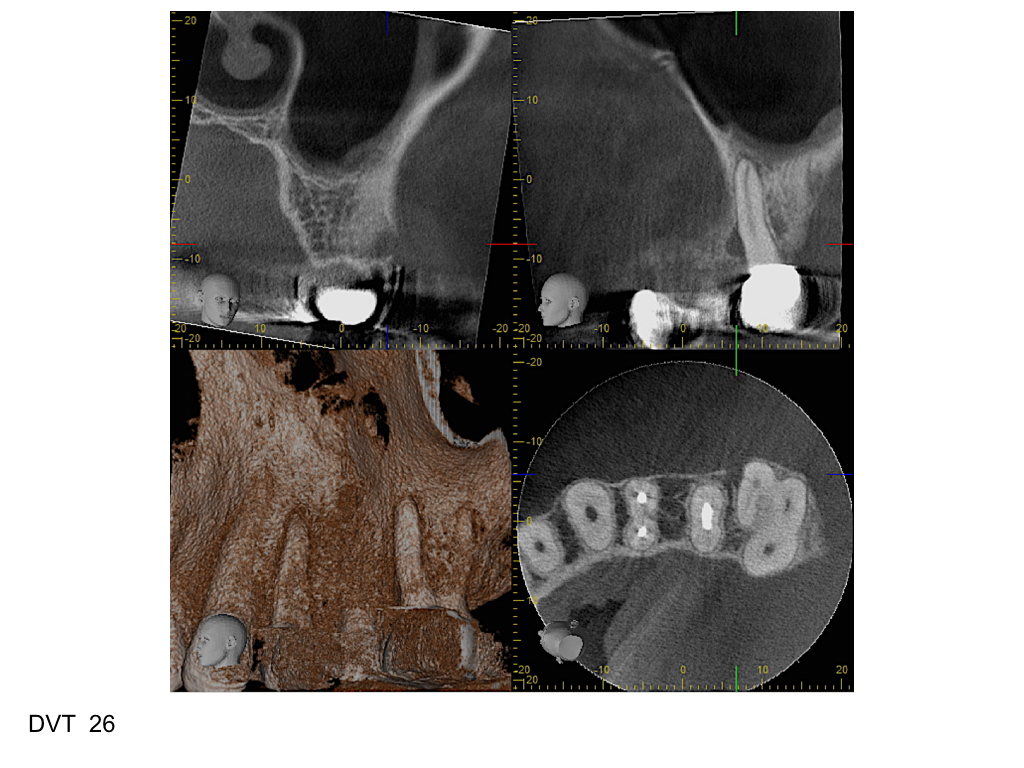

WS15_11.005 Veröffentlicht 3. November 2015 am 1024 × 768 in Fistel mit unklarer Ursache – 2D versus 3D